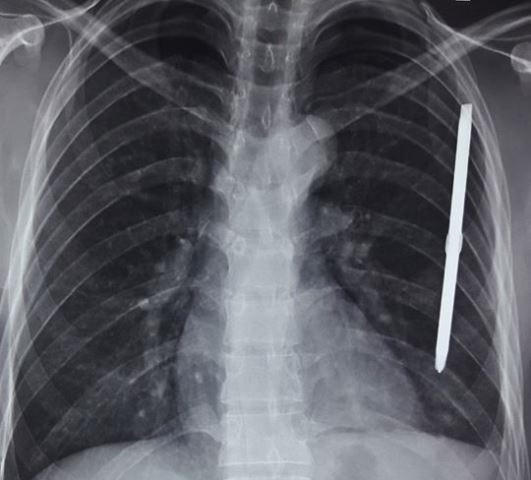

Ngay lập tức, người nhà đã đưa bệnh nhân đến bệnh viện. Qua thăm khám, các bác sĩ phát hiện một dị vật dài chính là tuốc nơ vít khoảng 20cm đi xuyên vào thành ngực trái bệnh nhân. Ngay lập tức, bệnh nhân được mổ lấy dị vật nằm trong phổi trái ra. Sau 5 ngày điều trị, sức khỏe bệnh nhân đã ổn định, có thể xuất viện.

Bác sĩ Phan Văn Hùng - Phó trưởng Khoa Ngoại Tổng hợp - BVĐK tỉnh Hà Tĩnh người trực tiếp phẫu thuật cho bệnh nhân N cho biết, trường hợp bệnh nhân N rất may mắn vì hướng đi của dị vật không đi trúng vào tim và không trúng các mạch máu lớn, mặt khác dị vật này có kích thước dài nên trong quá trình phẫu thuật các phẫu thuật viên cũng dễ dàng phát hiện vị trí và lấy ra nhanh chóng.